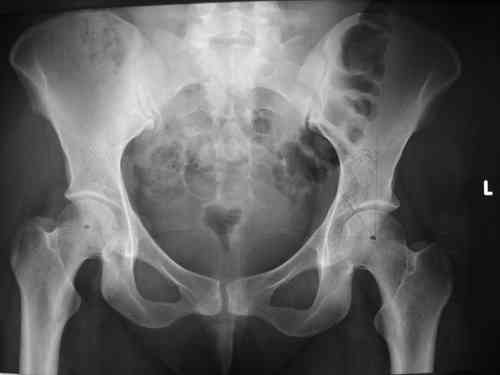

и 8месяцев после операции

> Результат через 10 дней и 8месяцев после операции

Да, забыл сказать - отличная работа, искренне восхищаюсь. Кость рубите по Judet (немного не разобрался по рисунку)?